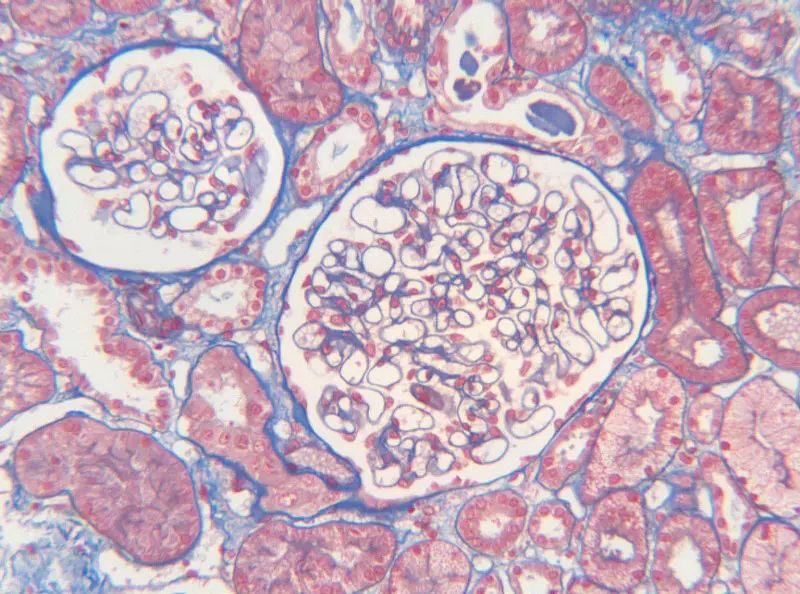

人腎組織